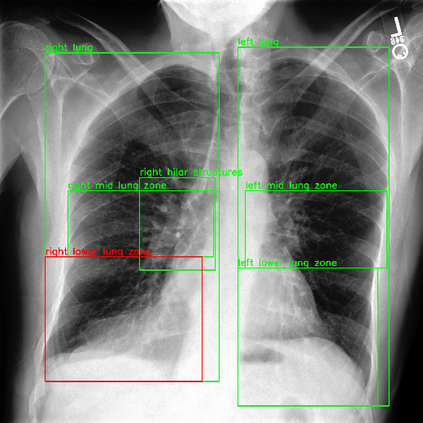

Despite the progress in utilizing deep learning to automate chest radiograph interpretation and disease diagnosis tasks, change between sequential Chest X-rays (CXRs) has received limited attention. Monitoring the progression of pathologies that are visualized through chest imaging poses several challenges in anatomical motion estimation and image registration, i.e., spatially aligning the two images and modeling temporal dynamics in change detection. In this work, we propose CheXRelNet, a neural model that can track longitudinal pathology change relations between two CXRs. CheXRelNet incorporates local and global visual features, utilizes inter-image and intra-image anatomical information, and learns dependencies between anatomical region attributes, to accurately predict disease change for a pair of CXRs. Experimental results on the Chest ImaGenome dataset show increased downstream performance compared to baselines. Code is available at https://github.com/PLAN-Lab/ChexRelNet

翻译:尽管在利用深层学习实现胸前射线解释和疾病诊断任务自动化方面取得了进展,但连续的胸前X射线(CXRs)之间的变化受到的注意有限。通过胸前成像可视化的病理进展监测在解剖运动估计和图像登记方面带来了若干挑战,即在空间上对两种图像进行匹配,在变化检测中模拟时间动态。在这项工作中,我们提议CheXRelNet,这是一个神经模型,可以跟踪两个CXRs之间的纵向病理变化关系。CheXRelNet包含当地和全球的视觉特征,利用图像间和图像内解剖学信息,并学习解剖区域属性之间的依赖性,准确预测两对CXR的疾病变化。Chest ImaGenome数据的实验结果显示,与基线相比,下游的性能有所增加。代码可在https://github.com/PLAN-Lab/CexRelNet上查阅。